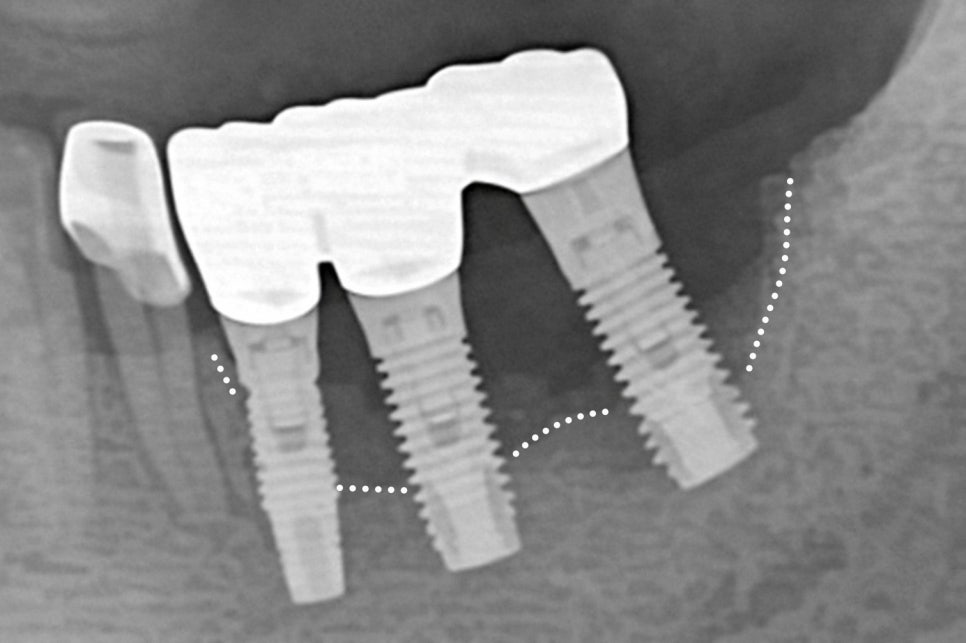

반면 임플란트 는 치조골에 직접 결합되는 구조로

이 과정에서 치주인대가 존재하지 않기 때문에

완충 역할을 하지 못합니다.

이는 저작력을 치조골이 직접적으로

받게 된다는 것을 의미하며,

과도한 압력이 가해지면 픽스처가

손상될 수 있는 위험을 증가시킵니다.

과한 힘이 가해지면 주변 치조골이 손상될 수 있으며

이를 방지하기 위해서는 교합 조정이 필요하며

정기 검진을 통한 꾸준한 관리가 이루어져야 됩니다.

따라서 픽스처를 심기 전에는

치주질환 치료가 선행되어야 됩니다.